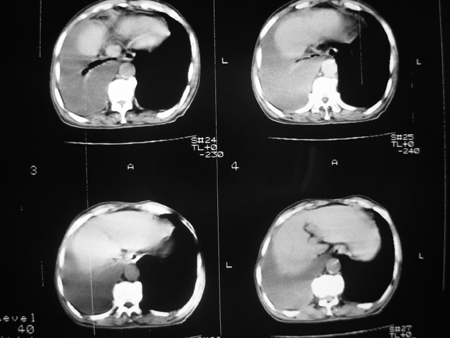

男77岁,胸痛就诊

右侧胸腔积液,部分包裹,右下肺膨胀不全,右下肺感染。

右侧胸腔积液,部分包裹,右下肺膨胀不全

右侧胸腔积液部分包裹伴右下肺膨胀不全。